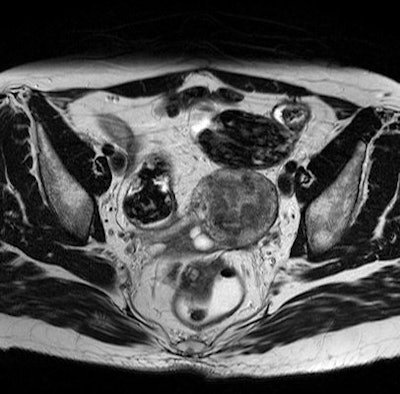

Endometriomas may be found in places such as on the ovaries, on the bowel wall, or on the bladder. Removal by surgical intervention is the standard treatment.

"Endometriomas can take on a variety of phenotypes, including cysts and adhesions, which adds to the difficulty of identifying them in MR images," Wenzel said.

Nevertheless, in the study, the experts detected 81% of 392 tissue samples of varying sizes verified by pathologists.

MRI proved to be particularly reliable in the detection of endometriomas in the rear abdominal cavity and, with a detection rate of 90%, on the colon. This is significant because endometrial tissue is frequently overlooked in that region. In a number of cases, endometriomas grow into the colon wall and are difficult for the surgeon to see.

Benefits of utilizing MRI include the fact that, for cysts, the technology shows metabolites, allowing to identify the age of the cysts and to differentiate endometrial from other types of cysts.